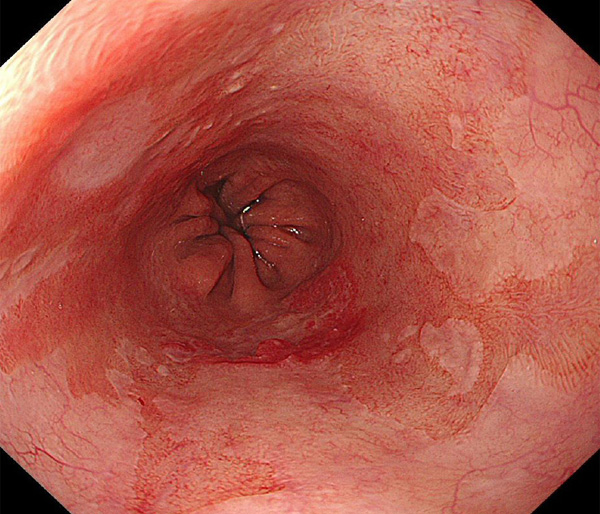

内視鏡所見と病理組織像の1対1対応が可能な症例を公募いたします。主にLSBEに発生した早期癌(HGDを含む)を対象としますが、興味深い症例であればSSBE癌でも結構です。採否は世話人へご一任ください。

症例呈示希望者は応募用紙に記入の上、代表的な内視鏡(2枚)、切除標本(新鮮、固定)、切り出し図、マッピング、代表的組織像とともに、Barrett 食道研究会事務局 barrett.shinshu@gmail.comへお申し込み下さい(10MB以下でお願い致します)。

特に、本邦では極めて稀なlong segment Barrett’s esophagus(LSBE)から発生した早期癌は、診断に難渋する場合も多く、欧米ではランダム生検による検出が標準的とされています。背景のBarrett食道もろとも全体を内視鏡切除+ラジオ波焼灼する欧米と異なり、ESDで内視鏡的な局所切除が基本の本邦では、存在診断+範囲診断(特に水平)を的確に行うことが不可欠です。

そのためには、一流の病理医による組織学的診断とエキスパート内視鏡医による拡大内視鏡像との一対一対応を徹底的に行うことで、『本来、見えないであろう拡大所見の先にある組織構築像が診えてくる』所まで内視鏡診断レベルを上げていく必要があります。その実現には、一対一対応を追究した症例(特にLSBE発生例)1例でも多く経験するしかありません。本研究会でBarrett食道腺癌(LSBE発生早期病変)を共に学び、拡大内視鏡像の一歩先を診るスキルを習得しましょう!一人でも多くの皆様のご参加をお待ちしています。

2026年1月24日開催の第19回研究会でご提示した検討症例です。 (画像をクリックすると拡大します)